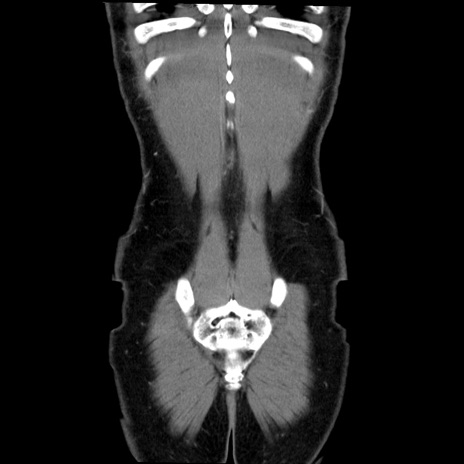

症例36(冠状断像)

【症例】20歳代 男性

【主訴】心窩部痛

【現病歴】今朝より上腹部痛あり。一旦軽快していたが再度出現したため救急要請。昨日夕に白身の魚を含む刺身を食べた。

【身体所見】BP 136/89mmHg、HR 74/min、BT 37.0℃、腹部:膨満、軟、心窩部に圧痛あり。反跳痛なし、筋性防御なし、腸雑音やや亢進あり。

【データ】WBC 17700、CRP 0.48